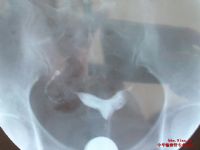

乌鲁木齐天伦不孕不育医院根据子宫畸形治疗的安全性、快速原则,开创宫腹腔镜下子宫畸形矫正术:通过巨资引进的德国宫腹腔镜系统,能一目了然、清楚直观地发现马鞍形子宫具体病征,诊断的同时可对症施治,具有微创、安全、无痛、恢复快的特点,极大限度确保了患者的子宫完整性和正常生理功能。【在线咨询】

宫腹腔镜下子宫畸形矫正术较常见和效果好的适应症是对称型马鞍形子宫,凡反复流产的这类病人均宜及早施术。手术中在宫腔镜的引导下把两个分开的子宫角,从一侧宫角至对侧宫角作一横切口,对半切开肌壁,将左右两侧切口面对缝一起。